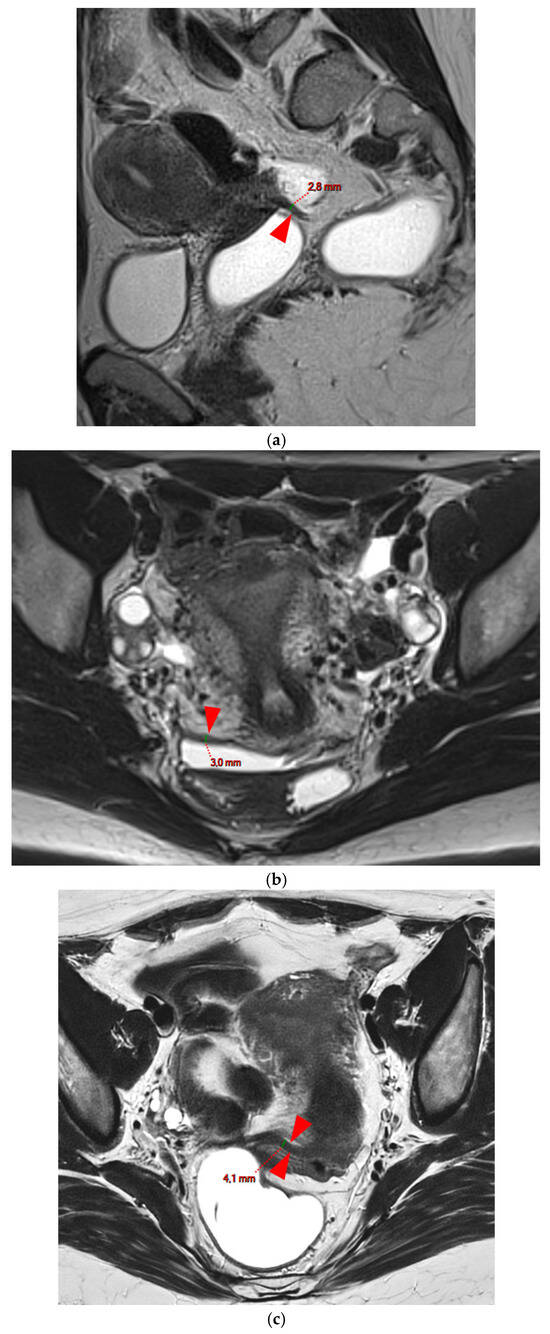

A type 3 USL appears as thickened (i.e., >2 mm), and can be classified either as type 3A (PPV = 75%; FPR = 25%) or as type 3B (PPV = 80%; FPR = 20%).

HTD Type 3A USL

A type 3A USL (Figure 3) maintains a smooth appearance with regular margins and often retains a tapering shape despite its thickening.

Figure 3. Pelvic MRI scans of three patients with thick (>2 mm), smooth, and regular USLs (HTD type 3A). (a) Sagittal T2WI: a thick (2.8 mm), smooth, tapering-shaped left USL (arrowhead). (b) Axial T2WI: regularly thickened (3 mm) right USL with a smooth surface (arrowhead). (c) Axial T2WI: regularly thickened (4.1 mm) right USL with a smooth surface (arrowheads).